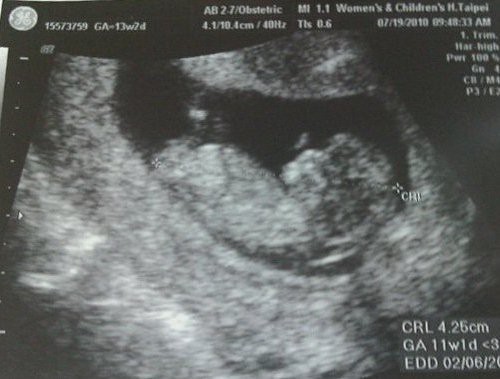

科學家在胎盤的胎兒側發現了空氣污染微粒,這顯示胎兒可能直接暴露於車輛交通和燃料

燃燒產生的黑碳。

這份刊登於《自然通訊》(Nature Communications)期刊的研究首次證實,母親吸入的

空污微粒可以穿透胎盤。作者從每個研究對象的胎盤中都能觀察到每立方公釐數千個微粒

科學家還檢查了流產者的胎盤,發現這些微粒甚至存在12週齡的胎兒中。